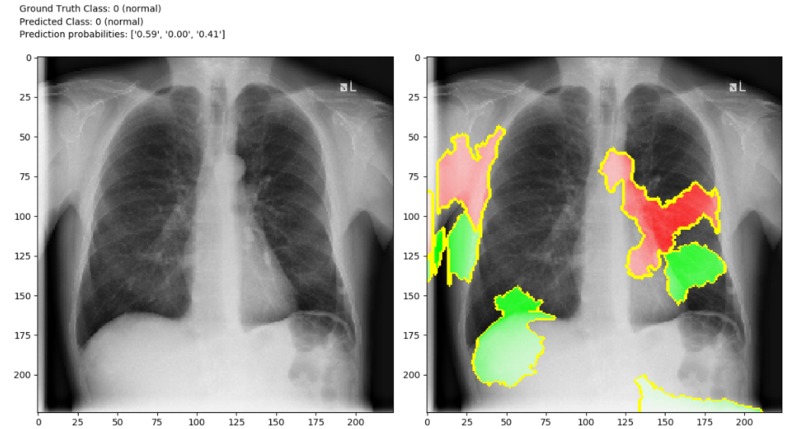

Although there is one drawback that X-ray analysis requires a radiology expert and takes significant time. Which is precious when people are sick around the world. Therefore, developing an automated analysis system is requires to save medical professionals valuable time.we can identify the difference in those two images. So, we can create a software which can identify difference between those two images using image processing techniques and Artificial Intelligence. We can Train AI model with features of normal person’s X-ray data and COVID19 patient’s X-Ray image data.

Detection of COVID19 symptoms is not only essential but also difficult task as it is current pandemic. COVID19 affects the lungs so if we detect in few seconds it will save doctors and health workers valuable time.

The primary objective is to develop the automated system that will detect the symptoms of COVID19 using X-Ray image.The secondary objective is to identify case of COVID19 positive or negative. Our goal is to use X-ray or CT images to develop AI based approaches to predict and understand the infection. We will release these models using our open source Chester AI Radiology Assistant platform which is designed to scale to a global need by performing the computation locally.